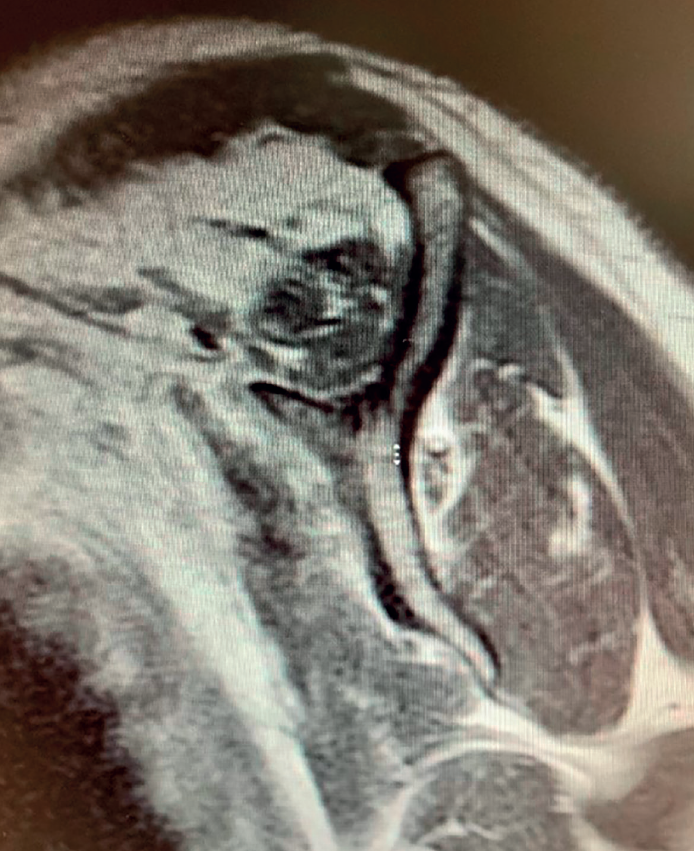

Boileau in 2005 or Simovitch in 2007(28,32) concluded that reverse replacement is unable to secure the restoration of external rotation. In many patients, only the teres minor will be able to afford active external rotation. If the teres minor presents rupture, retraction or adipose degeneration (which can be assessed by magnetic resonance imaging or computed tomography), we can predict a poorer outcome in these individuals, with an external rotation deficit(33,34). The lack of external rotation may prove quite disabling, especially in patients that use the arm in abduction. For this reason, some investigators such as Longo, in 2011(35), indicate the possibility of latissimus dorsi transfer to the reverse replacement implant, to restore external rotation in the patient.

Reverse shoulder replacement shifts the center of rotation distal and medial (Figure 5), increasing the lever arm of the deltoid muscle and recruiting more anterior and posterior fibers of the muscle, improving its function in patients without rotator cuff(1,19,20). In general, the patients can be expected to show increased anterior flexion and abduction of the shoulder. Having greater or lesser external rotation will depend on the quality of the teres minor and infraspinatus, among other factors (Figure 4). With regard to internal rotation in patients with reverse shoulder replacement after massive rupture, the results are less predictable and are conditioned by the implant design and the characteristics of the patient, among other factors. We must know the functional limitations of the implant and inform our patients about the results that can be expected.